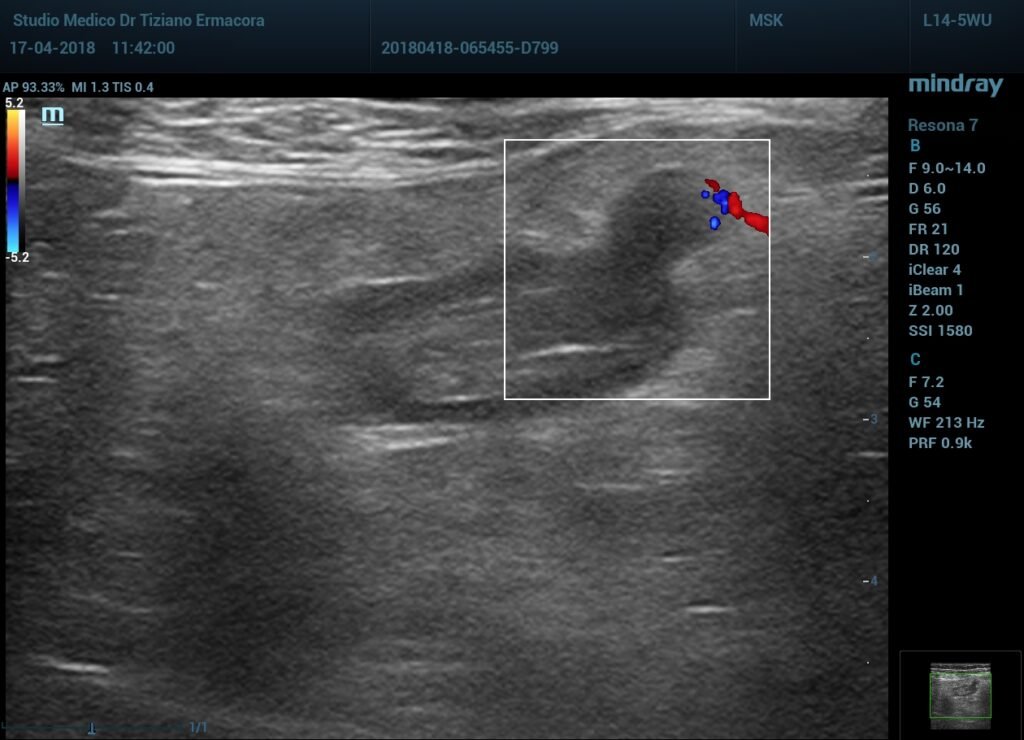

Infiltrazione ecoguidata della spalla

Con guida ecografica si riesce ad infiltrare la spalla nel punto esatto dove è presente…